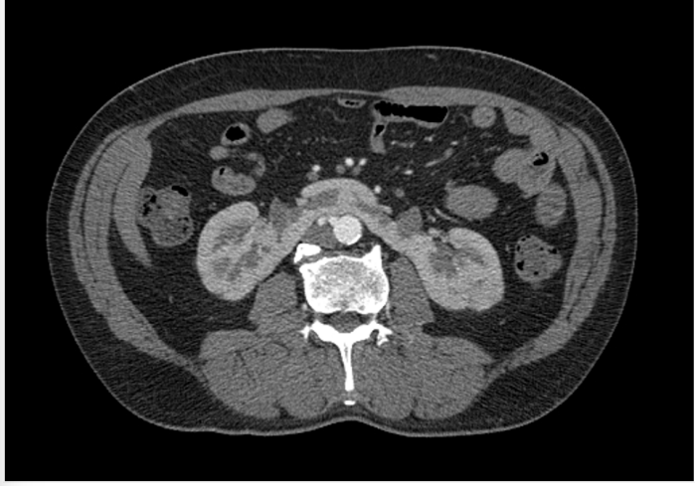

Figura 4 –Tomografia computadorizada do rim.

I- A imagem corresponde à anomalia de fusão denominada rim em ferradura, em que há a fusão dos polos inferiores dos rins na linha média.

III- Pacientes que apresentam esta anormalidade de fusão têm aumento da incidência de neoplasias, como carcinoma de células transicionais.

V- O local onde há a fusão pode apresentar tecido fibroso ou parênquima renal.